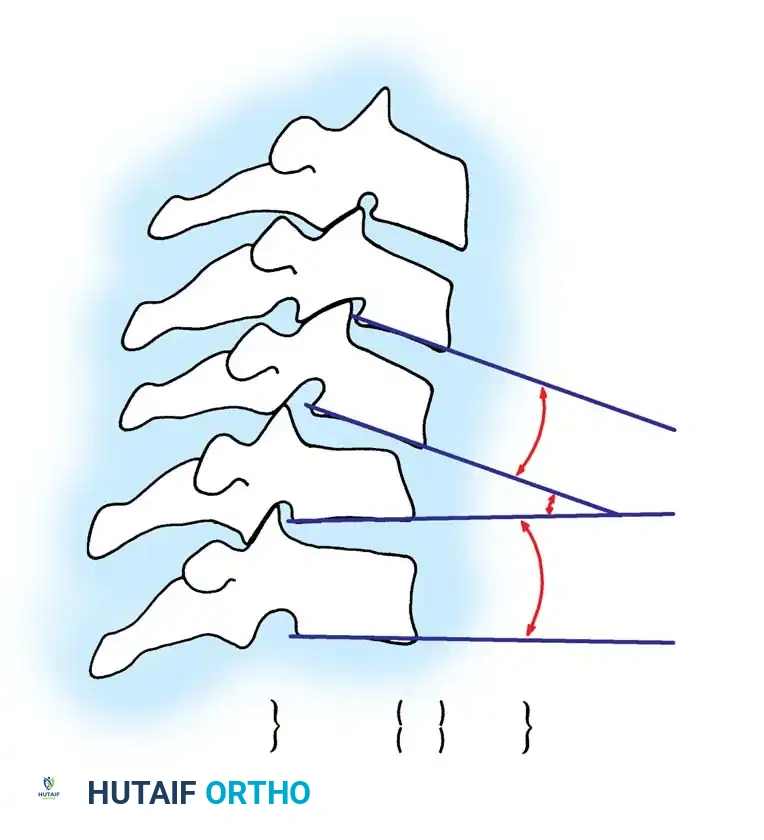

* Relative sagittal plane rotation > 11 degrees: 2 points

Fig 4. Sagittal plane rotation. An angular difference of more than 11 degrees between adjacent segments is a definitive marker of instability.